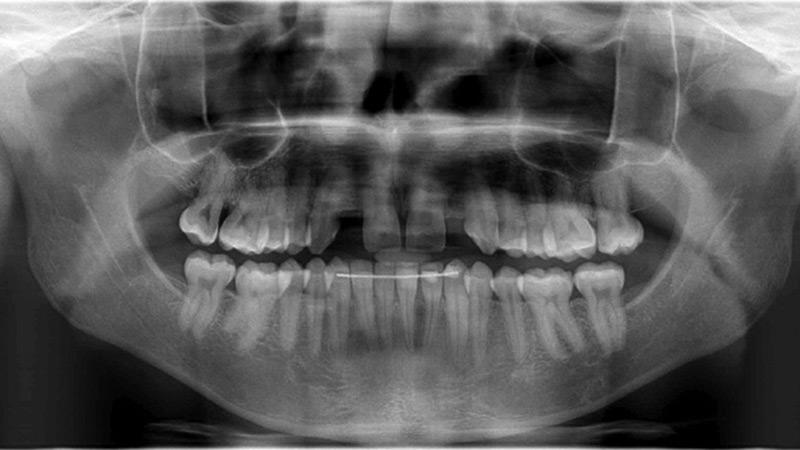

The Use Of Braces And Invisalign In Pre-Prosthetic Orthodontics

Hendler-3B2 alternate text for this image

Adult patients present with defined treatment goals and priorities. While some of them would like a full mouth rehabilitation, often their goals are more discrete and specific, looking to fix “just the one thing” that brought them into the office. As health care providers, we have to balance the patient’s wishes with their oral health … Read more